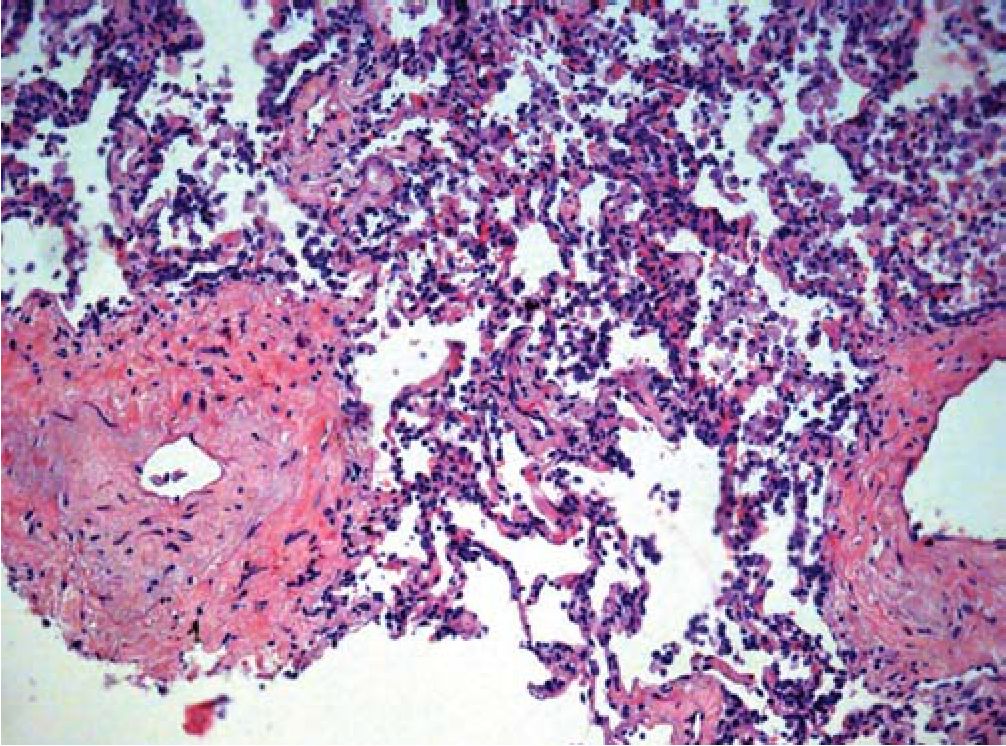

Рис. 4. Утолщение стенки мелкой ветви легочной артерии за счет фиброэластоза.

Окраска гематоксилином и эозином. X100

Стенки отдельных мелких сосудов слабо инфильтрированы лимфоцитами и эозинофилами, пролиферация эндотелиальных клеток.

Периваскулярные лимфоцитарные инфильтраты с примесью эозинофилов (рис. 5).